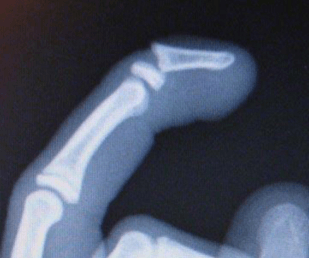

What is the appropriate Salter-Harris fracture classification of this fracture?

Type IV (through epiphysis, growth plate, and metaphysis)